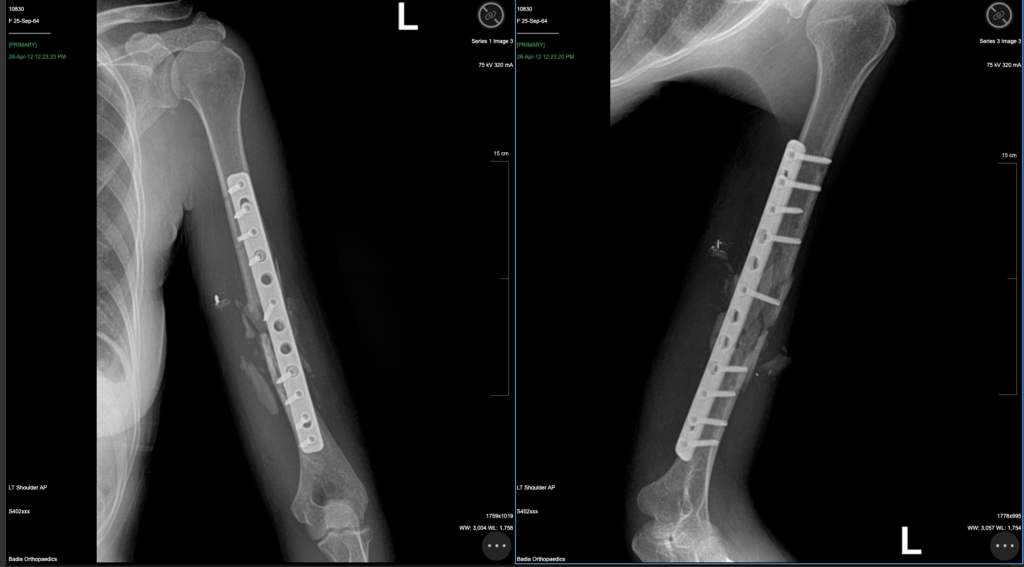

Dr. Badia, visited Haiti to support Chenet Audain in the race.